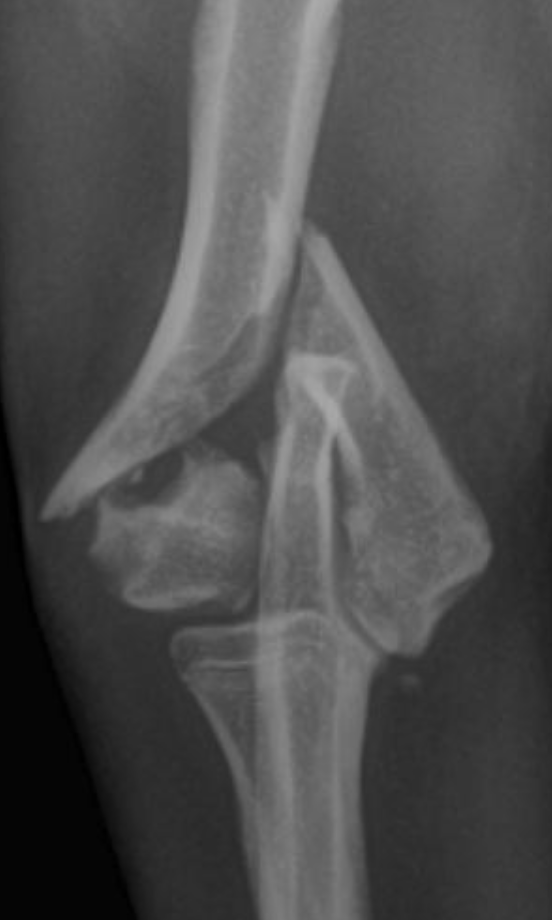

Humeral condylar fractures are one of the most common fore limb injuries in dogs. Prompt surgical repair is essential for the best long-term outcomes.

Humeral condylar fractures are breaks at the lower end of the humerus (upper fore limb bone) where it forms part of the elbow joint. This area has two rounded surfaces, or condyles — the medial and lateral — and the fracture can involve just one side (unicondylar) or split through both (bicondylar).

These injuries are relatively common in certain breeds and can occur even from low-impact events like falling or jumping down from furniture. Young dogs and breeds such as French Bulldogs are overrepresented. Spaniel breeds may also be affected due to

Humeral Intracondylar Fissure (HIF), where an incomplete fusion weakens the bone and predisposes it to fracture.

Dogs with humeral condylar fractures typically show sudden, severe limping after a fall or jump. The elbow is often very sensitive to touch, and the dog may hold the leg up and refuse to use it.

Diagnosis begins with an orthopedic exam. High-quality radiographs are essential. If the fracture is complex — particularly bicondylar fractures or suspected Humeral Intracondylar Fissure (HIF) — a CT scan may be recommended for a more complete view.

Prompt and accurate repair is critical. Surgery typically involves placement of a transcondylar screw to stabilize the fracture, often paired with plates or pins for additional support. Bicondylar fractures are especially challenging because the elbow is effectively split into three pieces, requiring meticulous reconstruction.

Humeral condylar fractures require surgeons with extensive experience and specialized tools. At AOCF, advanced imaging (CT and fluoroscopy) helps us understand the fracture before and during surgery. We maintain a full range of implants for even the most complex repairs and use minimally invasive techniques when appropriate. This approach ensures precise reconstruction, faster recovery, and the best possible long-term outcome for your pet.